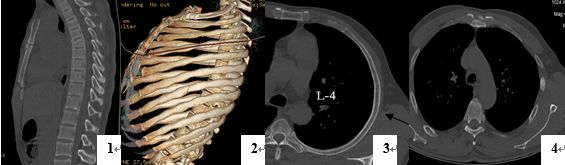

诊断骨关节外伤疾病哪家强 还看ct三维成像检查

诊断骨关节外伤疾病哪家强 还看ct三维成像检查 每日头条

骨关节外伤诊断哪家强 Ct三维成像有优势 北京安通医疗官网

16层螺旋ct多种重建方法在诊断肋软骨骨折中的应用 罕见病 疑难病 会诊平台 专家会诊 网上会诊 医学影像

肋骨骨折 你漏诊了吗 螺旋ct三维重建在胸廓骨折中的应用价值

128层螺旋ct三维重建在胸部外伤肋骨及肋软骨骨折诊断中的应用 中国期刊网

多层螺旋ct后处理重建在肋骨和肋软骨骨折诊断中的临床应用 中国期刊网

16层螺旋ct多种重建方法在诊断肋软骨骨折中的应用 罕见病 疑难病 会诊平台 专家会诊 网上会诊 医学影像

16层螺旋ct多种重建方法在诊断肋软骨骨折中的应用 罕见病 疑难病 会诊平台 专家会诊 网上会诊 医学影像

多层螺旋ct三维重建技术诊断创伤性肋骨骨折的临床价值分析 参考网

多层螺旋ct三维重建技术在胸部外伤的诊断价值